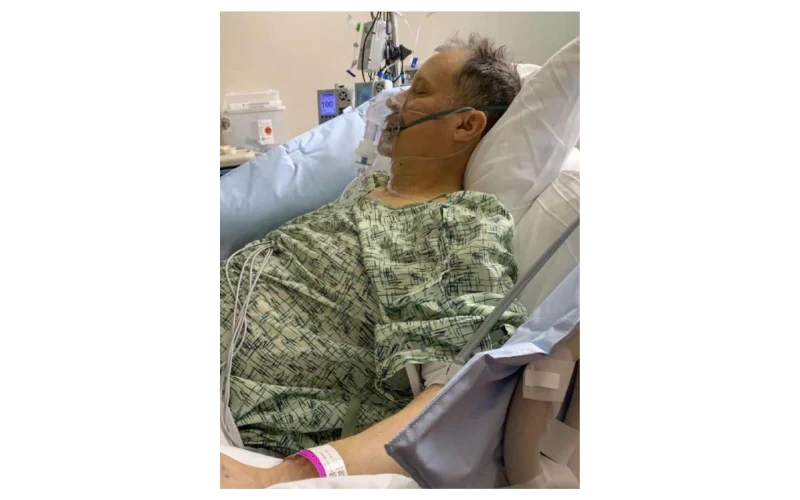

“l’ve spent most of my career on construction sites, constantly exposed to dust and airborne pollutants. Over time, it caught up with me-l developed COPD. At first, it was just mild shortness of breath, but the symptoms slowly worsened.l found myself coughing regularly, wheezing, and relying on an inhaler just to get through the day. Even climbing stairs became a challenge. My doctor warned me that if l didn’t take action, my condition could severely impact my quality of life.”

“By the fourth week, the tightness in my chest had lessened dramatically.l had more energy, and my doctor was surprised to see such a reduction in lung inflammation. Even my family noticedl wasn’t using my inhaler as much and seemed more active and upbeat.”

Now, seven weeks in, l can say with confidence that Mullein Aroma Diffuser has changed my life. My lungs feel stronger. The coughing,wheezing, and constant fatigue are gone.l can walk. play with my kids, and enjoy the outdoors again-without struggling to catch my breath. This product gave me back the ability to live fully.l recommend it to anyone battling COPD or breathing difficulties.lt brought me not just relief_but real hope.“

Max Winters- California